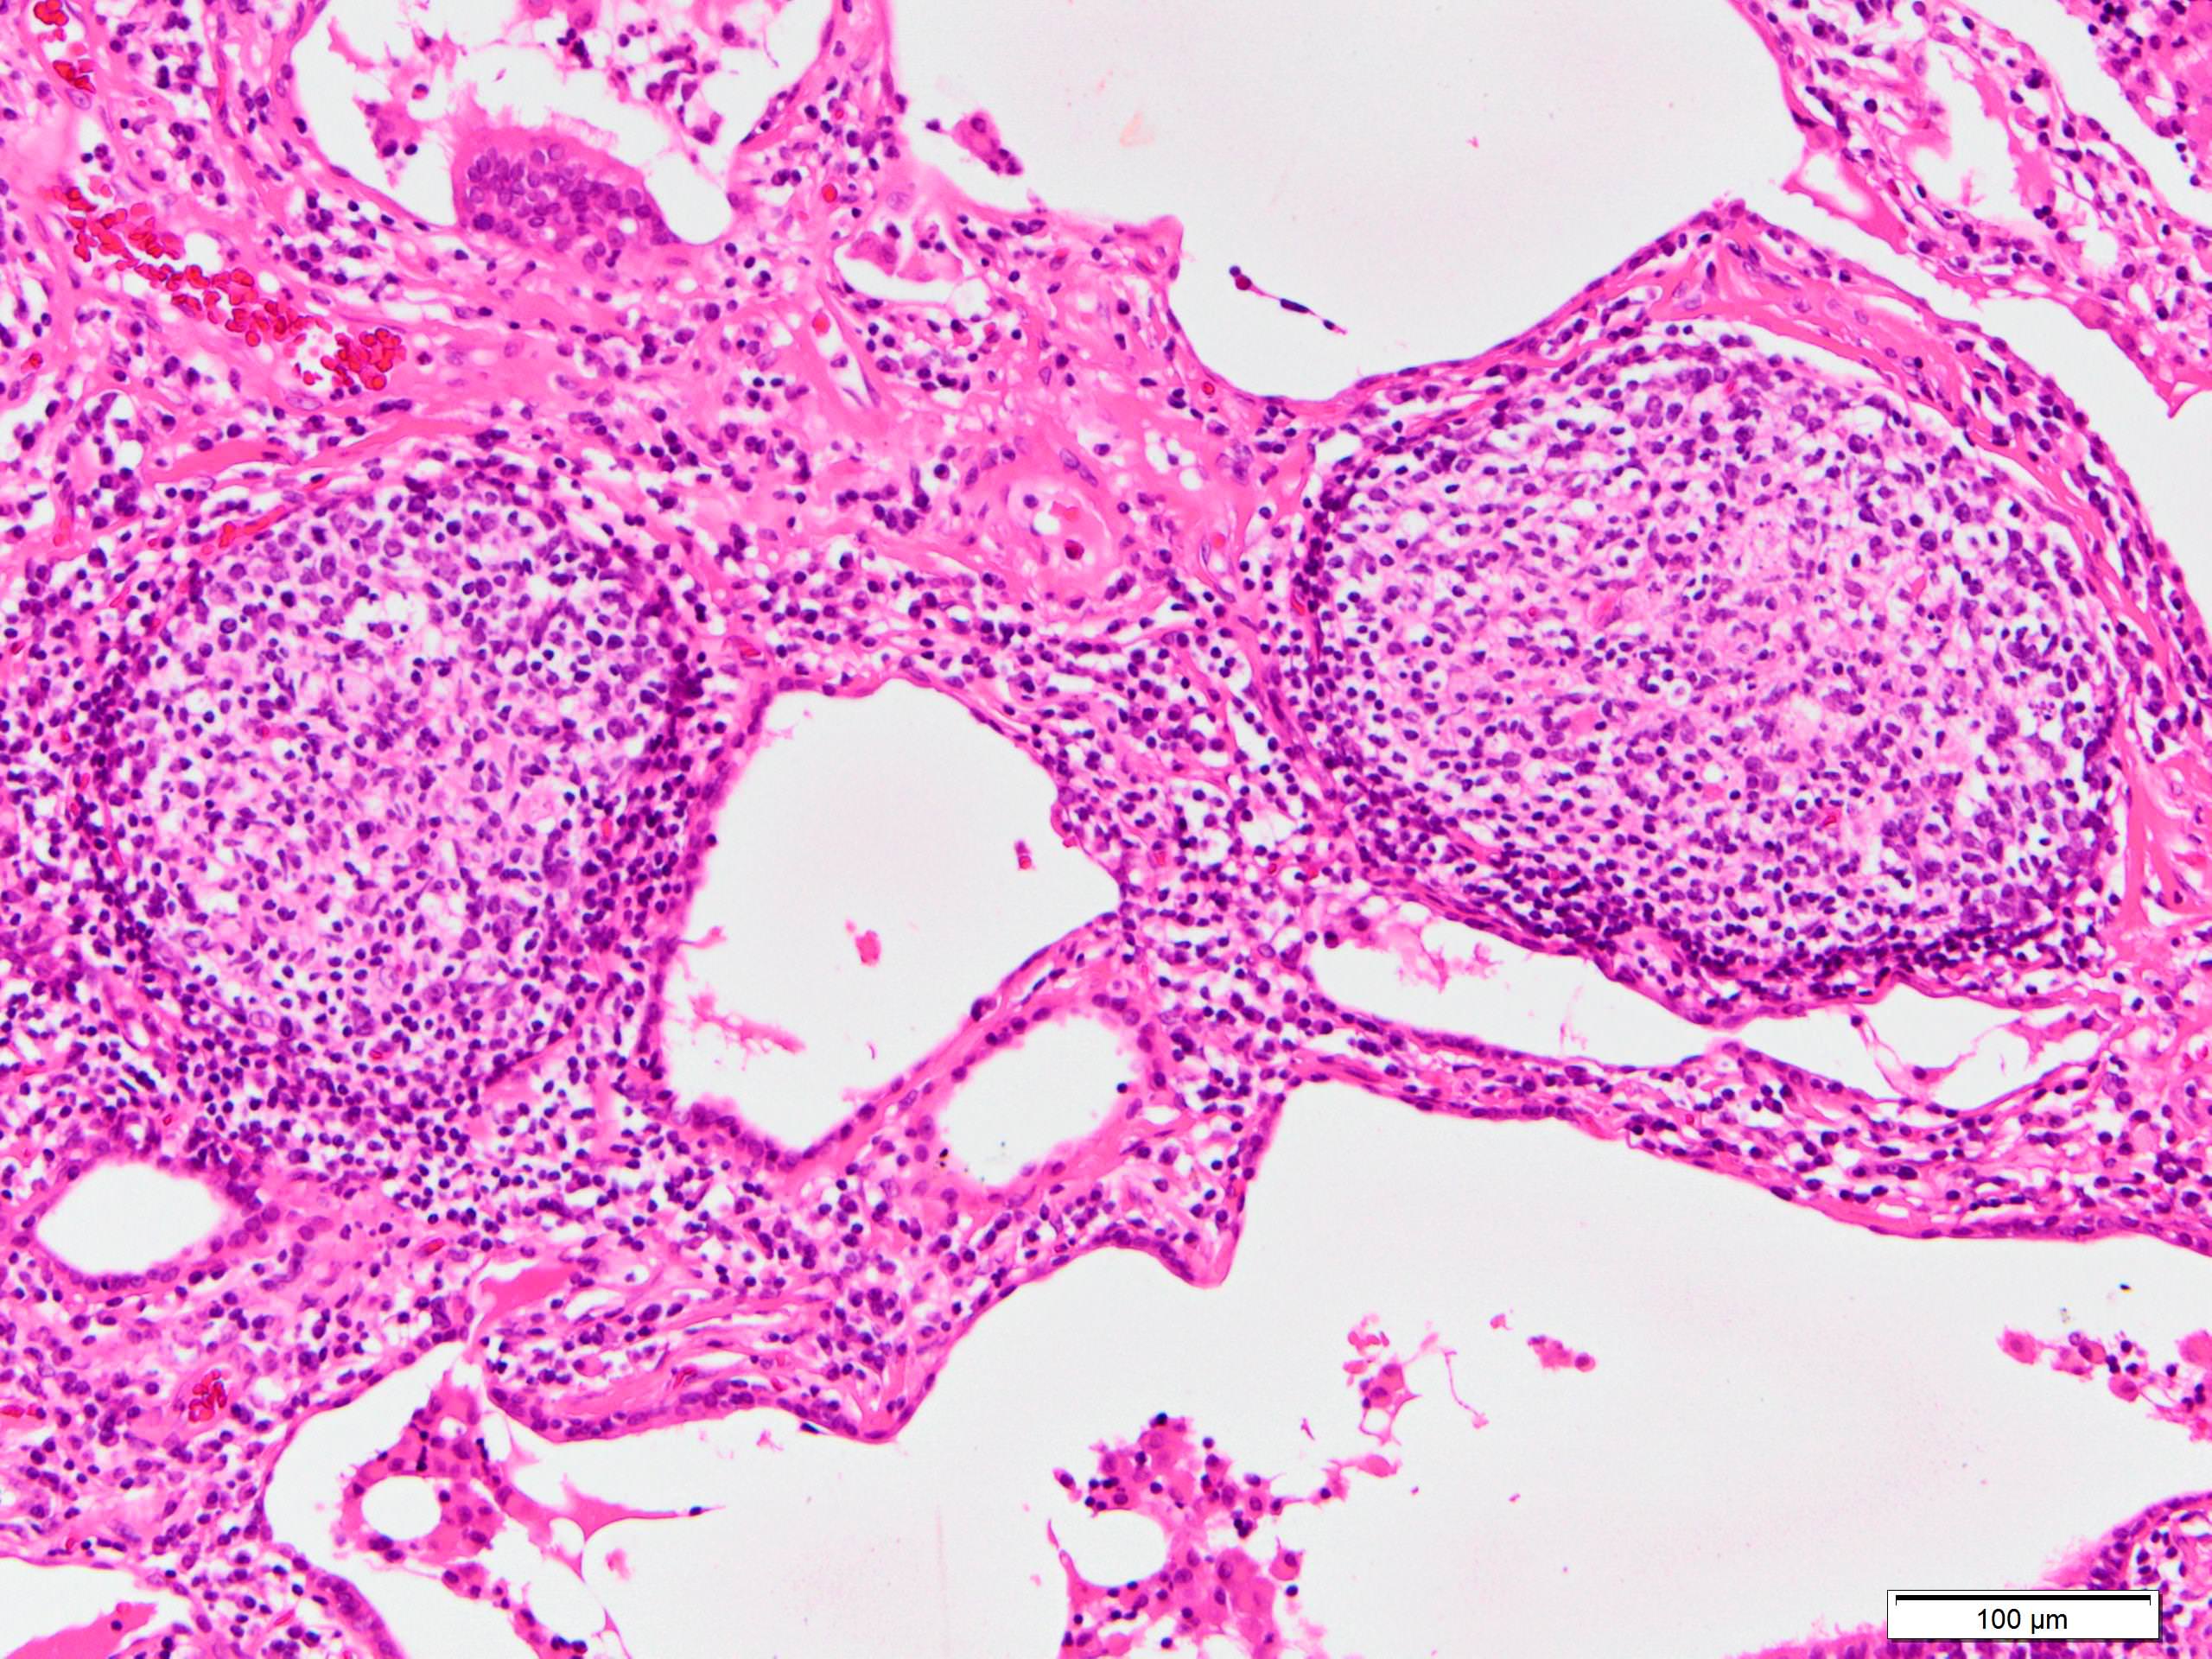

Microscopic (histologic) description

- Since there are few specific findings for NSIP pattern, it is essential to exclude other lung diseases on histology (Am J Respir Crit Care Med 2008;177:1338)

- Characteristic findings of NSIP pattern

- Diffuse and uniform inflammation ("temporal homogeneity") on low power of alveolar wall, bronchovascular bundles and pleura

- There are usually no normal alveolar walls in the affected lobules

- Cellular or fibrotic change

- Lymphocytic or plasmacytic infiltration

- Loose fibrosis

- Lung architecture is frequently preserved

- "Cellular NSIP" or "fibrotic NSIP" can be stated specifically in pathologist report

- Diffuse and uniform inflammation ("temporal homogeneity") on low power of alveolar wall, bronchovascular bundles and pleura

- Features of interstitial pneumonia with autoimmune features (IPAF) (Chest 2010;138:251):

- Lymphoid aggregates with germinal center

- Extensive pleuritis

- Prominent plasmacytic infiltration

- Dense perivascular collagen

Microscopic (histologic) images

Scroll to see all images.

Contributed by Akira Yoshikawa, M.D.

Images hosted on other servers:

Contributed by Akira Yoshikawa, M.D.

Images hosted on other servers: